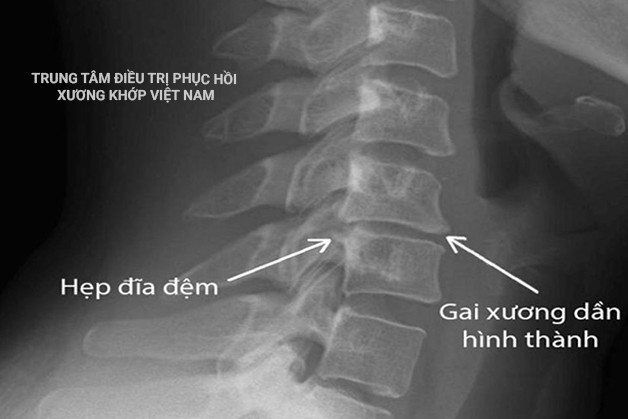

Câu chuyện bắt đầu từ tháng 11 năm 2014, khi ấy là vào đợt rét đại hàn, trời lạnh buốt căm căm, ông Lợi nhận thấy những cơn đau âm ỷ và dai dẳng ở vùng cột sống và thắt lưng, đặc biệt ông nghe thấy các tiếng lục cục lục cục mỗi khi cử động càng ngày càng trở nên rõ rệt hơn và cảm giác đau dọc từ lưng dưới xuống đến chân. Ông đi chụp x-quang ở bệnh viện Bạch Mai thì biết mình đã bị thoái hóa hết 5 đốt sống lưng L1-L5 và đau dây thần kinh tọa.

Hình 2: Thoái hóa cột sống thắt lưng

Hình 3: Thoái hóa cột sống thắt lưng